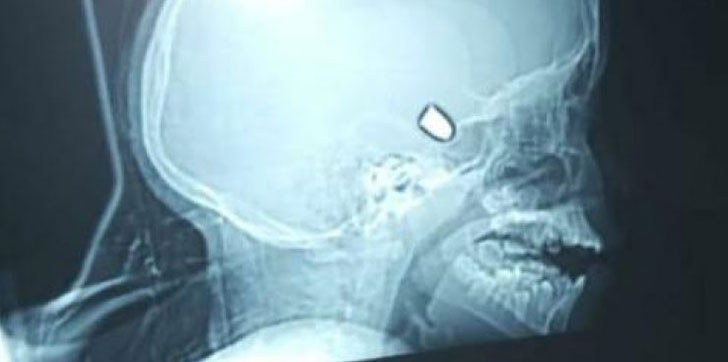

AZUA. – En estado de gravedad se encuentra una niña, tras impactar en su cabeza una bala perdida, este martes, en un hecho registrado en la localidad de Ansonia, Azua.

La menor, fue traslada al Hospital Ney Arias Lora de Santo Domingo, donde procedieron de manera inmediata a realizarle una tomografía, para saber dónde se encontraba la bala.

De acuerdo a informes preliminares, para está pautada una intervención a la menor, hija de la señora Negra Beltré, a los fines de extraerle el proyectil.